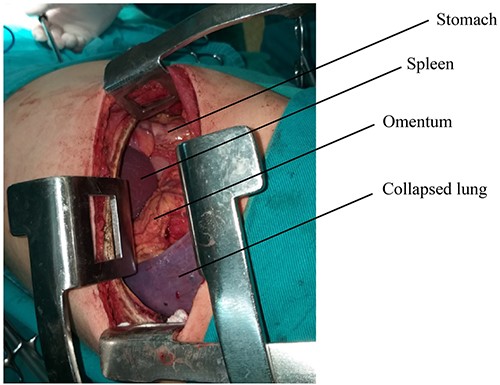

The surgical procedure was performed under general anesthesia with double-lumen tube and high airway pressure with low ventilation. Left lung was isolated, and a left lateral thoracotomy through the seventh intercostal space was performed. The spleen, stomach, omentum and part of the colon were found in the left chest, as shown in Fig. 3.